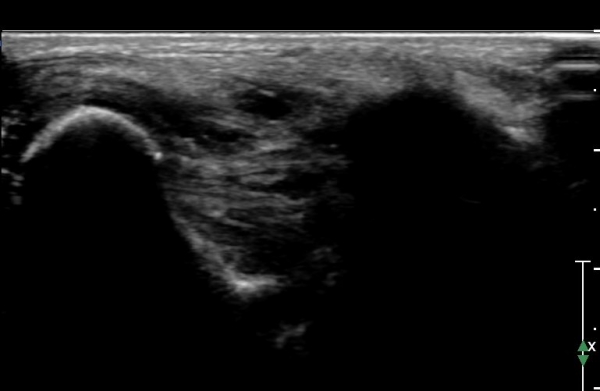

ÃÊÀ½ÆÄ °Ë»ç :  ¹ß¸ñ ¾ÕÂÊ Á¾´Ü¸é°Ë»ç¿¡¼­ ƯÀÌ ¼Ò°ß º¸ÀÌÁö ¾Ê´Â´Ù(»çÁø 1)